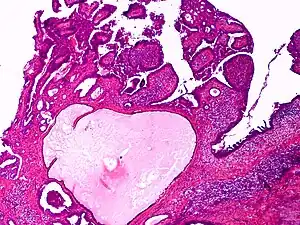

Apocrine gland carcinoma

Apocrine gland carcinoma is a cutaneous condition characterized by skin lesions which form in the axilla or anogenital regions.[1]: 670

| Apocrine gland carcinoma, papillary type | |